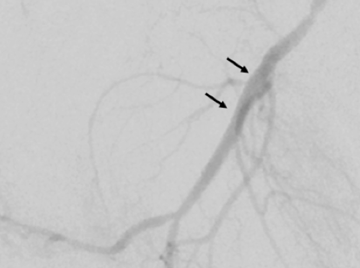

03. Nach der Weitung durch den Ballon kann die geweitete Arterie ein Stück weit zusammenfallen. Es bleibt also eine Engstelle. Diese sogenannte residuelle Stenose wird im nächsten Schritt mit einem Stent stabilisiert.

04. Nach erfolgreichem Setzen der Gefäßstütze ist die Verengung beseitigt. Um eine Wiederverengung bestmöglich zu vermeiden, ist der Stent mit Medikamenten beschichtet.